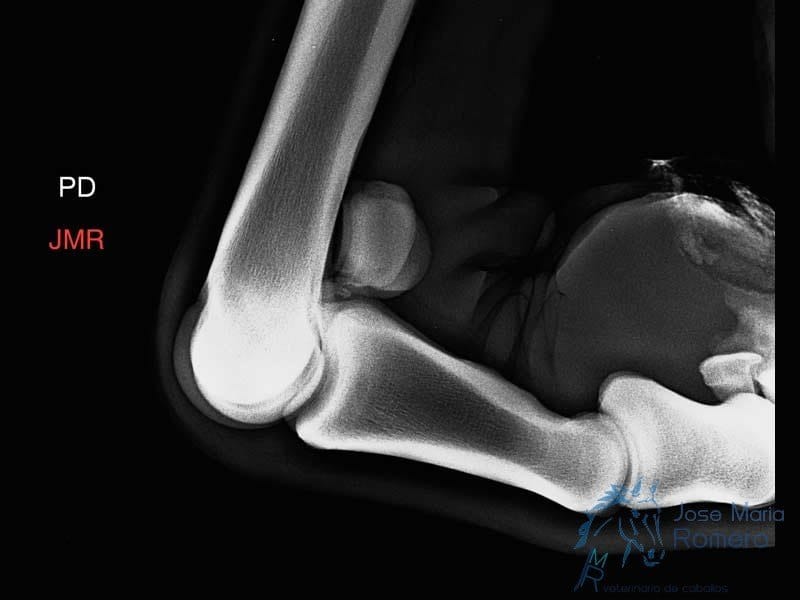

- Estudios radiológicos y/o ecográficos